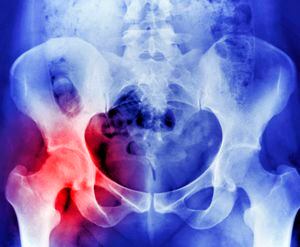

Los Institutos Nacionales de Salud de Estados Unidos precisan que cuando hay una deficiencia marcada de este nutriente se reduce la fuerza de los huesos e incrementa el riesgo de desarrollar osteoporosis, una enfermedad en que los huesos se vuelven débiles y corren más riesgo de enfrentar fracturas.

La citada fuente asegura que hay estudios que indican que las personas que consumen más alimentos ricos en vitamina K tienen huesos más fuertes y menos probabilidades de romperse la cadera que quienes consumen menos de estos alimentos.